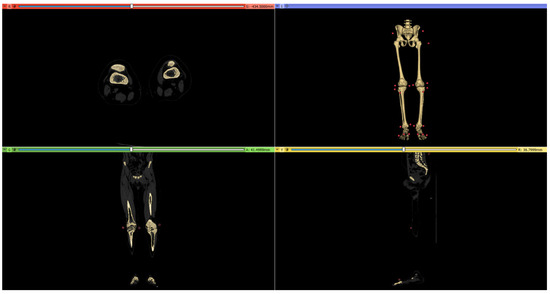

2.2. CT Scan Protocol

3.1. 3D Reconstruction of Patient-Specific CT Scan